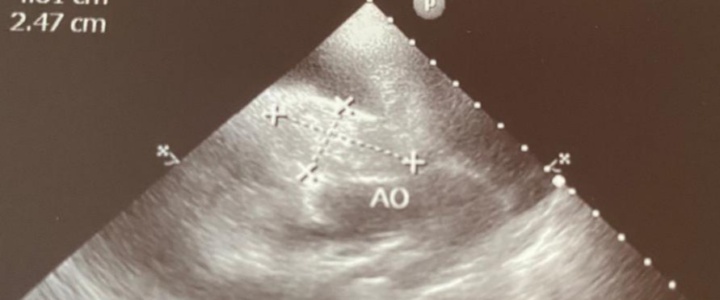

W dzisiejszym poście omówimy jedną z takich chorób: nowotwór serca psa. Bezpośredni asumpt do takich refleksji dała nam konsultacyjna wizyta kardiologiczna jednego pacjenta. Był to 9 letni owczarek niemiecki, który na początku marca poczuł się źle. Właściciel zauważył spadek aktywności i jego lekarz prowadzący skierował czworonoga do nas na konsultacje kardiologiczną ze względu na płyn w jamie opłucnej i otrzewnej. Diagnozą okazał się rozległy nowotwór serca. Jego rokowanie niestety było złe. Jak widać w tym przypadku nawet szybka reakcja nie zawsze pomoże naszym pupilom, ale aby dać im szansę badajmy nasze czworonogi i reagujmy, tak szybko, jak tylko to możliwe.

Pomocne bywają badania radiograficzne, echokardiograficzne i angiograficzne, rezonans i tomografia. Niewiele wnoszą natomiast badania krwi. Ostateczne postawienie diagnozy możliwe jest po dokonaniu biopsji mięśnia sercowego. Jednak najczęściej diagnoza zostaje postawiona dzięki pośmiertnym badaniu histopatologicznemu serca.